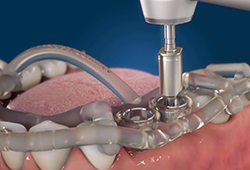

Если периодонтит не поддается консервативному лечению, то прибегают к хирургическим методам. Они необходимы при запущенных процессах, характеризующихся острыми болями и угрожающими состояниями. В большинстве случаев можно восстановить структуру зуба без его удаления. И чем раньше будет произведено лечение, тем больше шансов положительного результата.